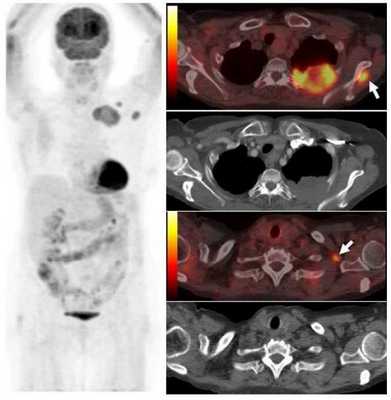

Опухоль левого легкого с частичным некрозом и деструкцией ребер. Визуализируются два метастаза в подключичных лимфоузлах и в мышцах (стрелки), которые на КТ не видны. Необходимо выполнить трансторакальную биопсию той части опухоли, которая расположена в периферических отделах, чтобы получить образец жизнеспособных тканей.

ПЭТ-КТ лимфоузлов: N-стадия

С помощью ПЭТ можно обнаружить метастатическое поражение лимфоузлов корней легких и средостения лучше, чем с помощью любого другого метода, так как метаболически активные лимфоузлы при ПЭТ-КТ, даже малого размера, характеризуются повышенным захватом ФДГ. Это справедливо и для тех случаев, когда морфологические признаки злокачественного поражения узлов могут не обнаруживаться на КТ-изображениях. Также метод позволяет оценить увеличенные лимфоузлы, не накапливающие или минимально накапливающие радиофармпрепарат, которые часто носят реактивный характер или отражают остаточные изменения в отсутствие опухолевого поражения. При определении стадии N чувствительность составляет 81% против 61% у КТ, и специфичность 90%, в то время как КТ характеризуется специфичностью 79%.

Наибольшее преимущество в оценке средостения — это возможность исключить злокачественное поражение любого лимфоузла с высокой степенью точности. То есть, отсутствие интенсивного захвата ФДГ лимфоузлом достоверно говорит об истинном отсутствии метастазов (прогностическое значение отрицательного результата равно 99%). В то же время не все лимфоузлы средостения, характеризующиеся повышенным метаболизмом, обязательно являются злокачественными; ложноположительный результат может быть обусловлен воспалительными изменениями. Это объясняет, почему изменения со стороны средостения должны оцениваться количественно с использованием SUV (стандартизированного уровня накопления). Пороговое значение SUV max в пределах 4,0-5,3 позволяет рассматривать изменения со стороны лимфоузлов средостения как положительные (то есть, метастатическое поражение есть).